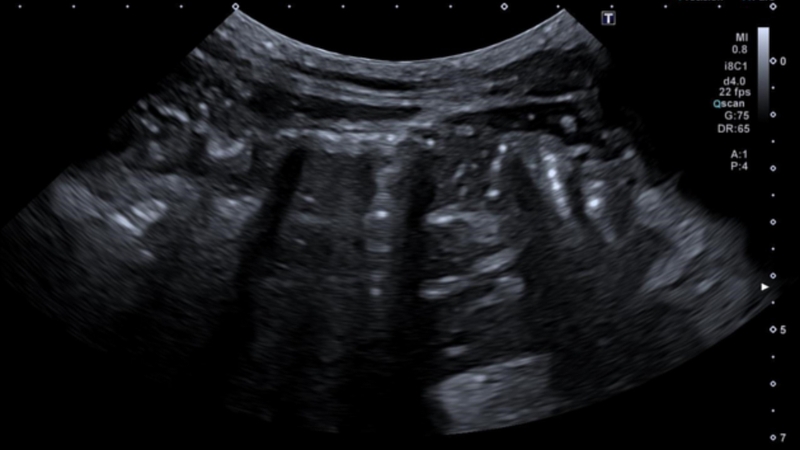

Hình ảnh viêm ruột thừa cấp trên siêu âm

Khi bị viêm, ruột thừa có những thay đổi đặc trưng mà bác sĩ có thể dễ dàng nhận diện thông qua hình ảnh siêu âm. Hình ảnh thường thấy của viêm ruột thừa cấp trên siêu âm có thể kể đến như: Đường kính ruột thừa gia tăng, không xẹp khi đè ép, thành ruột phù nề, thâm nhiễm mỡ và dịch xung quanh. Trong đó, thâm nhiễm mỡ được xem là dấu hiệu quan trọng nhất vì cho thấy tình trạng viêm.

Đặc điểm chung của hình ảnh ruột thừa cấp trên siêu âm

Một số đặc điểm chung của hình ảnh viêm ruột thừa cấp trên siêu âm có thể kể đến như:

• Ruột thừa giãn rộng: Đường kính ruột thừa vượt quá 6mm, đây là dấu hiệu quan trọng giúp chẩn đoán viêm ruột thừa. Lòng ruột thừa có thể chứa dịch hoặc mủ, làm giãn rộng thành ruột thừa. Nếu tình trạng viêm kéo dài, ruột thừa có thể chứa nhiều khí hoặc hình thành áp xe.

• Thành ruột thừa dày: Đây là một trong những dấu hiệu viêm cấp tính. Thành ruột thừa dày lên rõ rệt, thường lớn hơn 3mm. Quan sát thấy hiện tượng tăng sinh mạch máu tại vùng viêm khi sử dụng siêu âm Doppler màu. Thành ruột có thể mất cấu trúc bình thường do phù nề và viêm lan rộng.

• Dấu hiệu "Target Sign" (hình bia ngắm đặc trưng): Trên mặt cắt ngang, ruột thừa viêm tạo nên hình ảnh nhiều vòng đồng tâm, giống như bia ngắm. Cấu trúc này xuất hiện do sự chồng lớp của thành ruột thừa bị viêm và các mô xung quanh. Đây là một trong những dấu hiệu giúp bác sĩ phân biệt viêm ruột thừa với các bệnh lý khác ở vùng bụng dưới.

• Mất khả năng nén: Khi bác sĩ ấn đầu dò siêu âm lên vùng hố chậu phải, ruột thừa bình thường sẽ bị ép xẹp xuống. Tuy nhiên, khi bị viêm, ruột thừa không thể xẹp lại, do thành dày và có tình trạng phù nề. Dấu hiệu này đặc biệt hữu ích trong việc phân biệt viêm ruột thừa với các bệnh lý đường ruột khác.

• Sự xuất hiện của dịch tự do ở hố chậu phải: Dịch tự do quanh ruột thừa có thể xuất hiện, đặc biệt trong trường hợp viêm nặng hoặc vỡ ruột thừa. Nếu có khí trong ổ bụng, đây là dấu hiệu nguy hiểm cho thấy ruột thừa có thể đã thủng, dẫn đến viêm phúc mạc. Trong một số trường hợp, áp xe quanh ruột thừa có thể hình thành, khiến tình trạng viêm lan rộng.